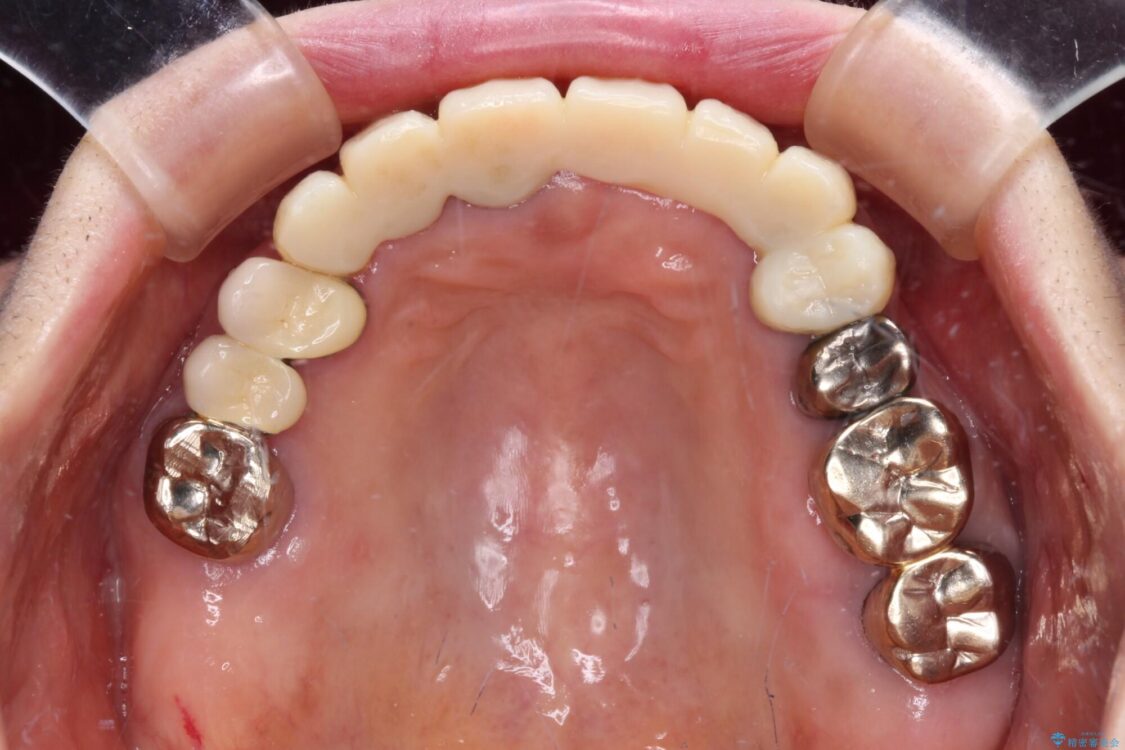

治療前

• 前歯をきれいにしたい インプラントや部分矯正を用いた総合歯科治療 治療前画像